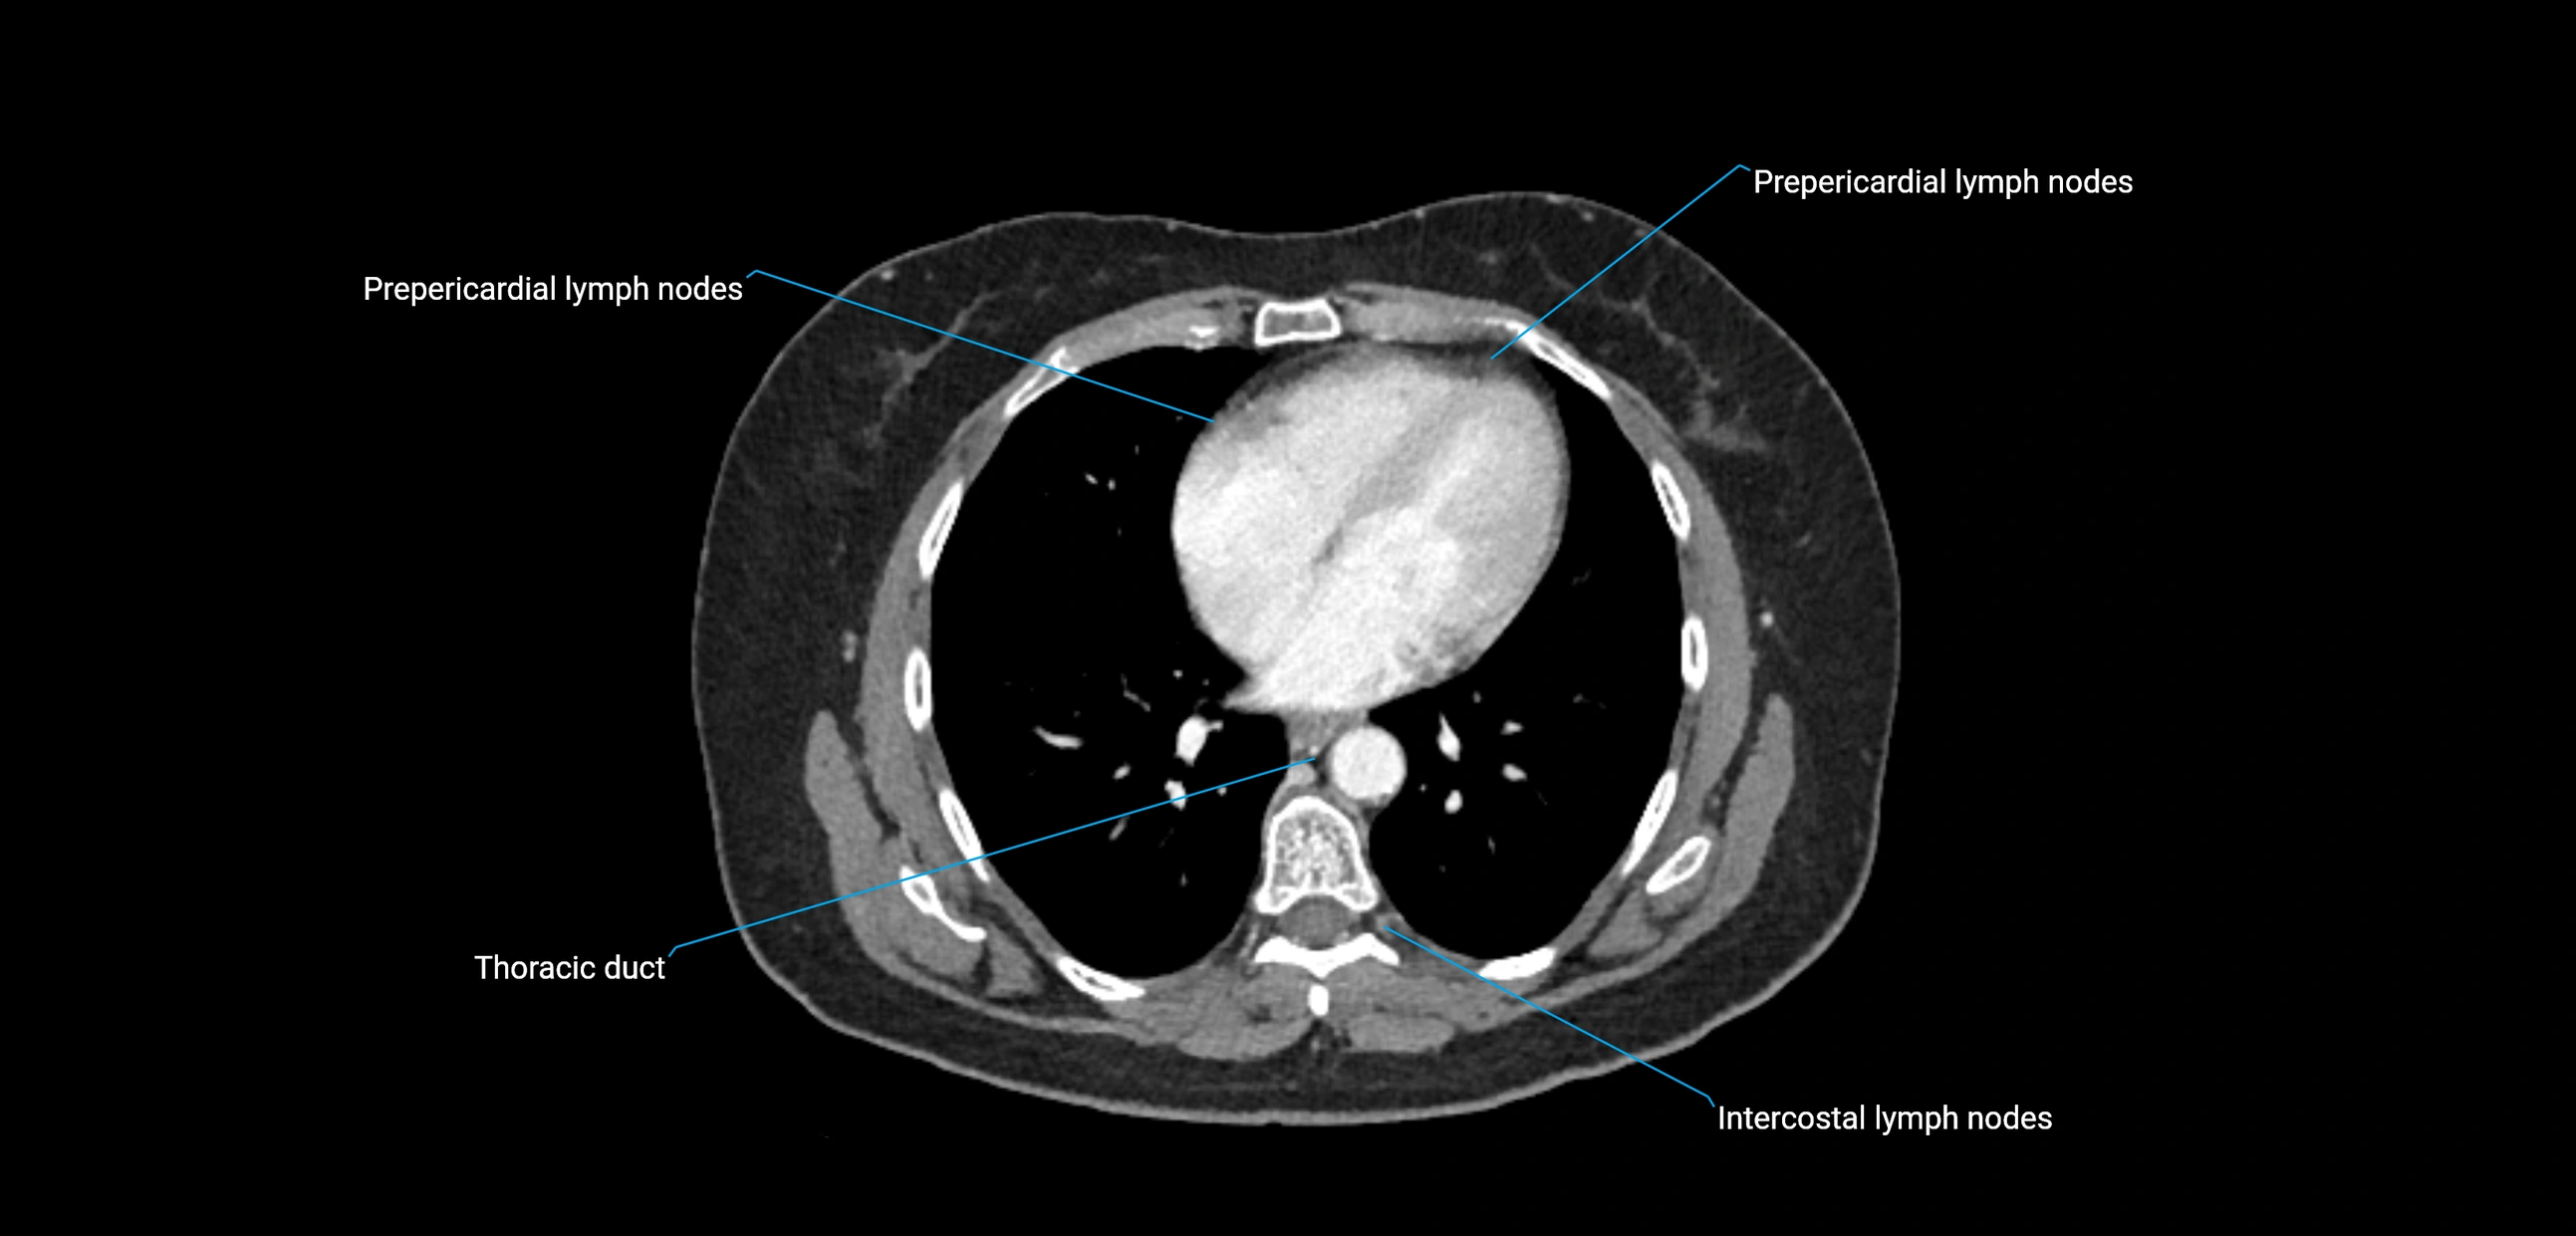

CT Appearance

CT Post-Contrast:

• Normal nodes enhance homogeneously

• Malignant nodes may show heterogeneous enhancement, central necrosis, or conglomerate formation

• Size >1 cm short axis is suspicious, though morphology and distribution are equally important

CT Venography (CTV):

• Demonstrates nodal encasement or compression of adjacent vessels (aorta, IVC, renal veins)

• Useful in staging testicular and ovarian malignancies

• Provides 3D reconstructions for retroperitoneal lymph node dissection planning